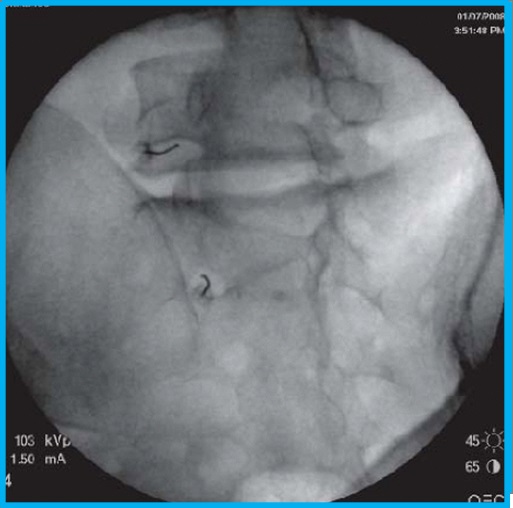

Στην ουραία επισκληρίδιο έγχυση υπό ακτινοσκοπική καθοδήγηση, εισάγεται ένας καθετήρας μέσω του ιερού τρήματος και προωθείται έως το επίπεδο στης κατώτερης οσφυϊκής μοίρας, όπου γίνεται η έγχυση διαλύματος τοπικού αναισθητικού και στεροειδούς.

Πρόκειται για μια ελάχιστα επεμβατική τεχνική λύσης μετεγχειρητικών συμφύσεων με εισαγωγής ενός εύκαμπτου ενδοσκοπίου στην οσφυϊκή μοίρα μέσω του ιερού τρήματος. Με χρήση διαλύματος υαλουρονιδάσης και φυσιολογικού ορού επιτυγχάνεται οι λύση συμφύσεων, με σύγχρονη απελευθέρωση των νευρικών δομών.

Πρόκειται για μια ελάχιστα επεμβατική νέα τεχνική αντιμετώπισης του μετεγχειρητικού πόνου με χρήση ενός διπολικού καθετήρα με εύκαμπτο, κατευθυνόμενο ενεργό άκρο, που διεγείρει νευρικές δομές του επισκληρίδιου χώρου μέσω χρήσης παλμικής ραδιοσυχνότητας. Μέσω αυτού μπορούν να εγχυθούν και διαλύματα για αναλγησία ή συμφυσιόλυση. Ο καθετήρας εισάγεται στον επισκληρίδιο χώρο μέσω του ιερού τρήματος.